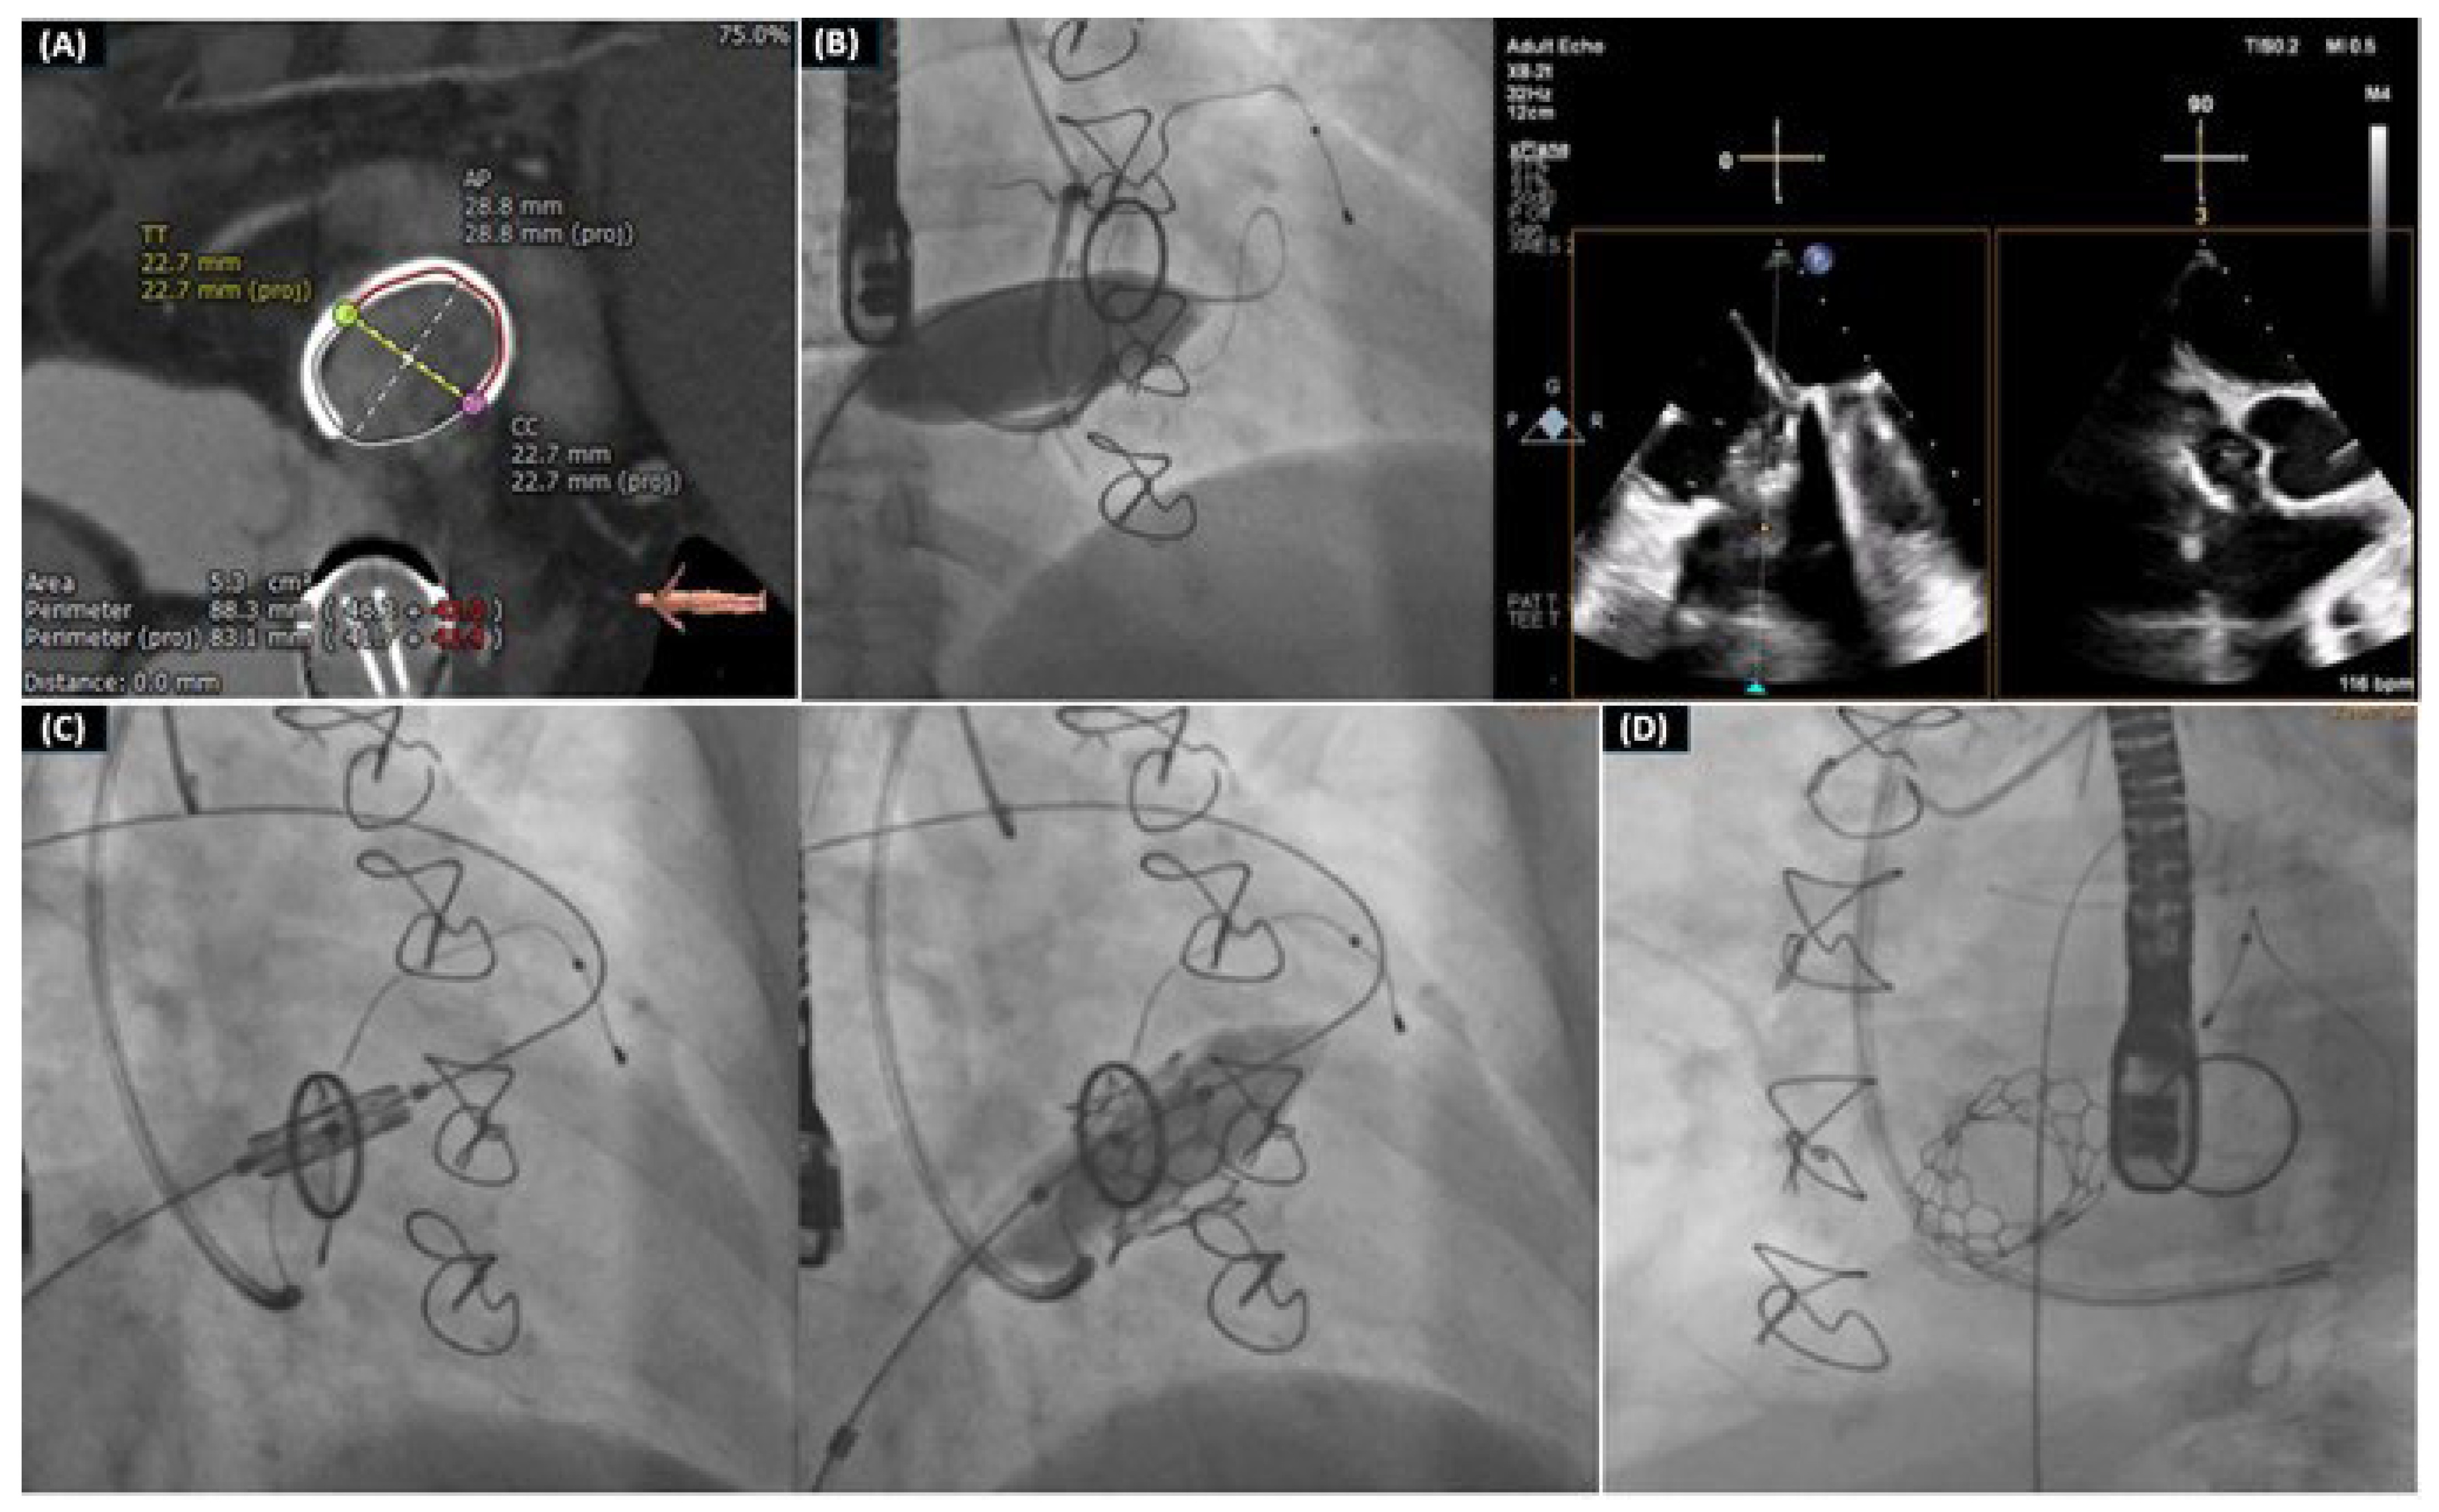

2.7. Transcatheter Mitral Valve Replacement (TMVR)

2.8. Mitral Valve-in-Valve (MVIV), Valve-in-MAC (TMVR in-MAC), and Valve-in-Ring (MVIR)

- Drakopoulou, M.; Latsios, G.; Synetos, A.; Benetos, G.; Soulaidopoulos, S.; Oikonomou, G.; Apostolos, A.; Aggeli, K.; Lozos, V.; Lymperiadis, D.; et al. Transcatheter mitral valve-in-valve replacement transeptally using a novel balloon-expandable device. J. Card. Surg. 2022, 37, 3376–3377. [Google Scholar] [CrossRef] [PubMed]

- Drakopoulou, M.; Oikonomou, G.; Latsios, G.; Synetos, A.; Benetos, G.; Simopoulou, C.; Apostolos, A.; Soulaidopoulos, S.; Aggeli, K.; Lozos, V.; et al. Takotsubo cardiomyopathy complicating transcatheter mitral valve-in-valve replacement. J. Geriatr. Cardiol. 2022, 19, 559–561. [Google Scholar] [PubMed]